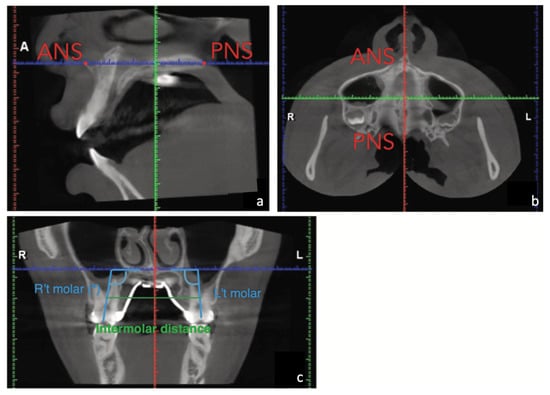

| JR-JL | 82.2 mm |

|---|---|

| AG-GA | 117.7 mm |

| Maxillomandibular transverse discrepancy | 35.5 mm |

| Expected transverse difference (14 y/o) | 18 mm |

| Maxillomandibular transverse differential index | 17.5 mm |